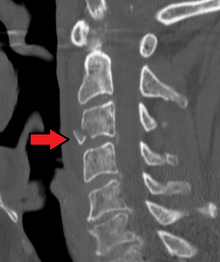

A fracture of the base of the dens (a part of C2) as seen on CT. | |

Severe pain will usually be present at the point of injury. Pressure on a nerve may also cause pain from the neck down the shoulders and/or arms. Bruising and swelling may be present at the back of the neck. A neurological exam will be performed to assess for spinal cord injury. X-rays will be ordered to determine the severity and location of the fracture. CT (computed tomography) scans may be ordered to assess for gross abnormalities not visible by regular X-ray. MRI (magnetic resonance imaging) tests may be ordered to provide high resolution images of soft tissue and determine whether there has been damage to the spinal cord, although such damage is usually obvious in the conscious patient because of the immediate functional consequences of numbness and paralysis in much of the body.